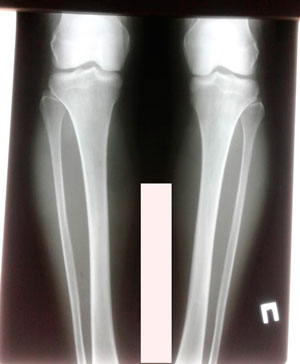

Дата операции - 24.10.2019г.

Дата снятия аппаратов - 22.01.2020

Срок сращения - 89 дней.